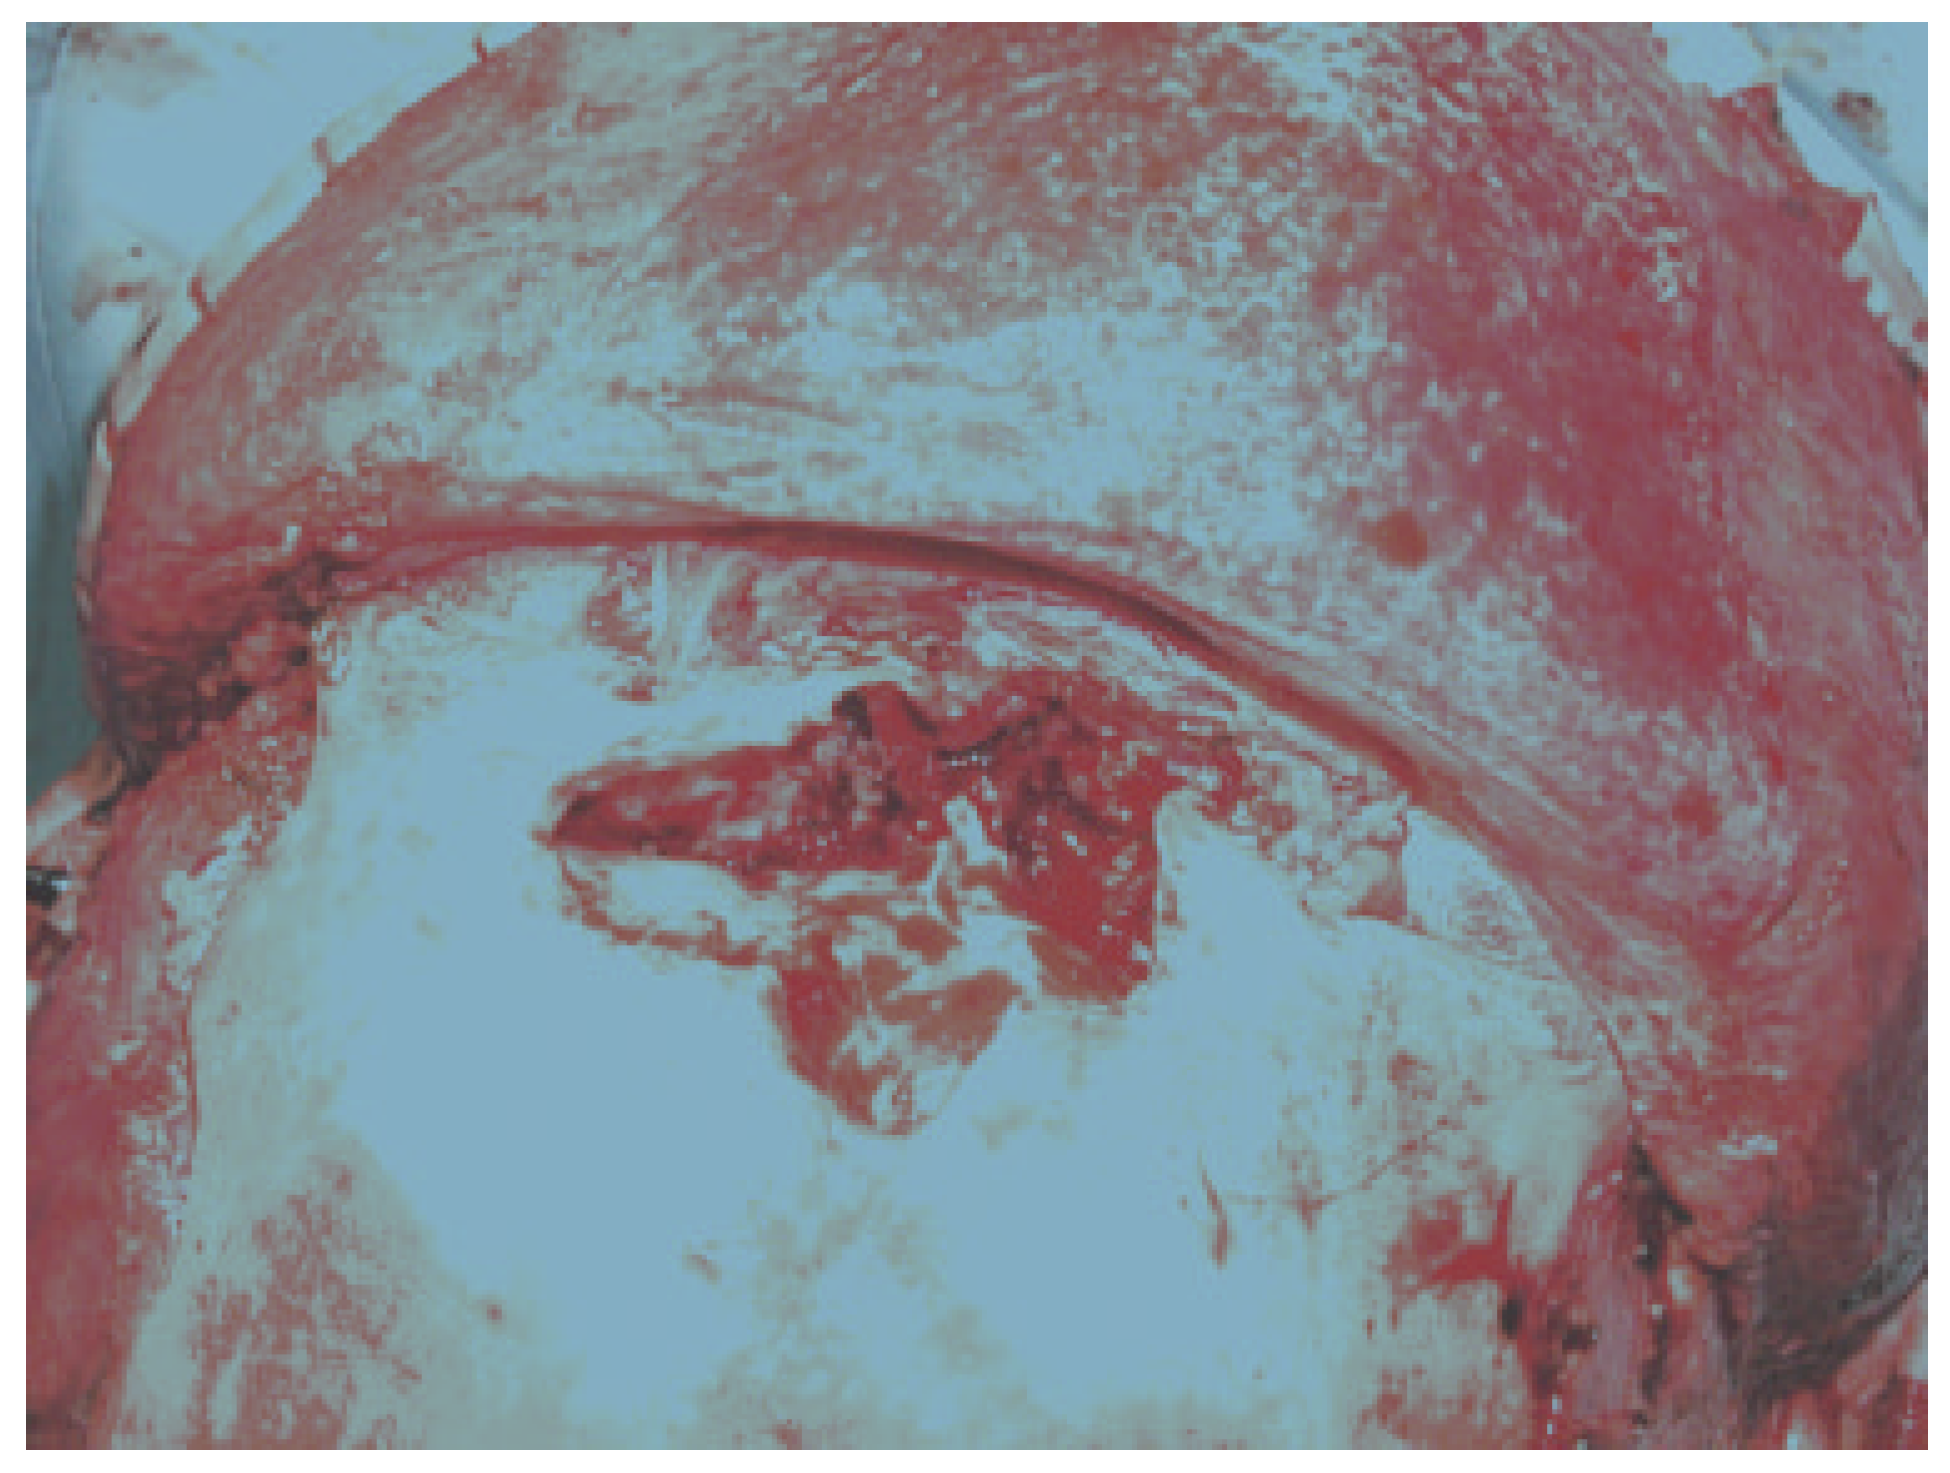

Figure 2.

Intraoperative photograph of anterior and posterior wall frontal sinus fractures with no CSF leak and destruction of the nasofrontal ostia (drainage system).